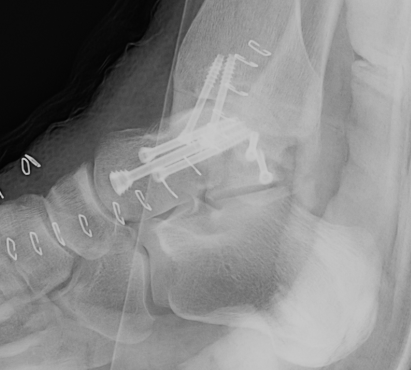

Xray

ORIF talar body utilizing medial malleolar osteotomy

Post ORIF of the nonunion utilizing a medial malleolar osteotomy